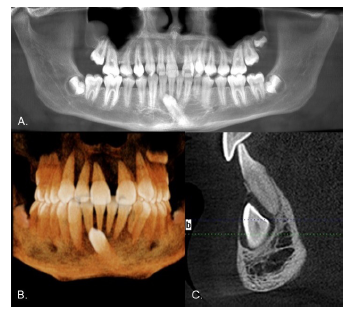

Case 1

Male, 12 years old. Clinical examination revealed that the inferior left canine was the only primary tooth still present (Fig. 1). The panoramic radiograph showed that the 3.3 was in a type 1 transmigration (Fig. 2A). The cone beam computed tomography (CBCT) showed that the crown of the transmigrated canine was very close to the adjacent incisors’ roots (Figs. 2 B and C). Despite the recommendation for surgical removal or even orthodontic traction, the parents chose not to treat the transmigrated tooth and instead to follow up with periodic radiographs.